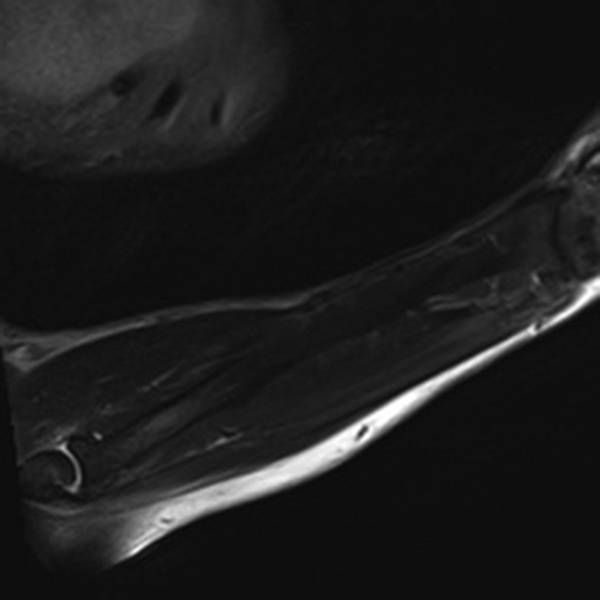

Motion Artifact. Degraded image quality of sagittal T1-weighted fat-saturated post-contrast MR image of the foot due to patient motion.